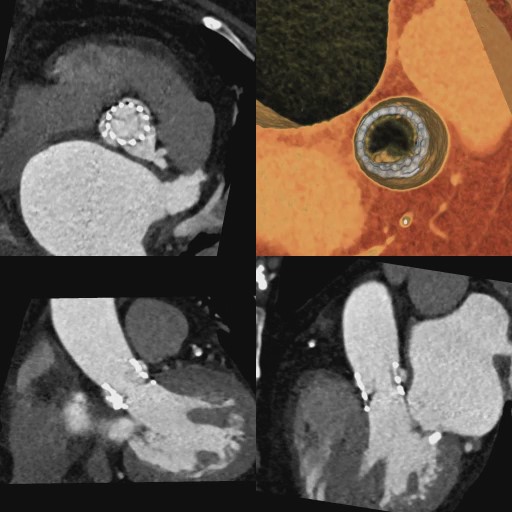

心臓弁膜症に対する治療法として、薬で症状を緩和し経過観察を行う保存的治療、開胸手術で心臓の弁の修復や交換を行う外科的治療、開胸せずに心臓を止めることなく、カテーテルを用いて弁を植え込むカテーテル治療という3つの治療法が選択肢となります。放射線科では、弁やその周囲の石灰化、血液循環の状態を調べて治療方法を決定するための重要な情報を提供します。また、弁の手術後の経過なども調べることができます。

経カテーテル大動脈弁植込み術(TAVI)施行前と後